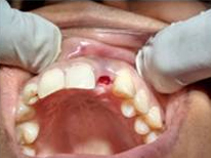

Use of Bone Graft & GTR membrane for an Implant

Bone Graft in Extraction Socket